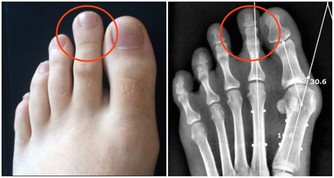

美國研究指出,擁有希臘腳的人患拇囊炎、錘狀指以及背部疾病的風險更高。

因為多數人站立或行走時,腳趾中拇指所受的重量最多,但是對於希臘腳來說,則是第二腳趾會被磨彎、磨平,進而導致腳部疾病的發生。所以擁有希臘腳的人更要注意鞋子的版型,在選擇鞋子時一定要穿起來舒適而且符合腳型,否則會對健康有更多負面的影響喔!